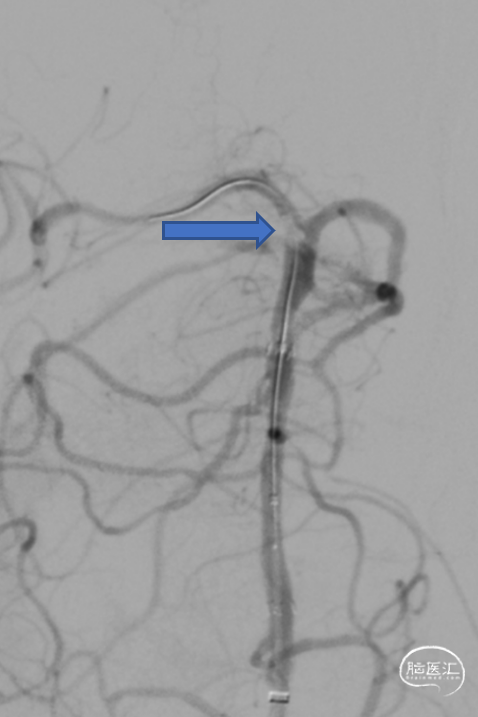

第二次拉栓后造影,血管再通,支架内再狭窄处理风险极高,且目前前向血流3级,对比造影时影像支架未有移位。

基底动脉支架内再狭窄导致的闭塞取栓风险高,操作复杂,Syphonet®取栓支架通体显影,可以清楚看见取栓支架与基底动脉内原有支架的关联,避免支架移位,提高手术安全。